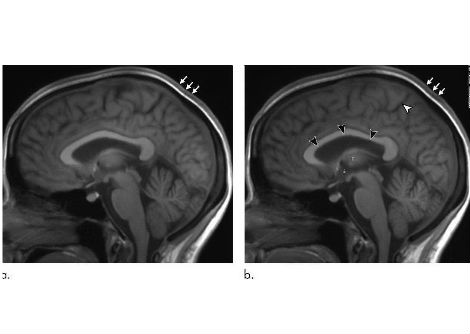

يُستخدم العمر البيولوجي لتقدير كفاءة وظائف الجسم مقارنةً بسنوات عمر الشخص الفعلية. تعتمد هذه القياسات على مثيلة الحمض النووي، وهي عبارة عن علامات كيميائية صغيرة تعمل كعلامات تنظيمية على الحمض النووي وتتغير تدريجيًا مع تقدمنا في العمر.

لتقدير العمر البيولوجي، استخدم الباحثون نوعين من التقييمات. ركز أحدهما على التغيرات الكيميائية في الحمض النووي التي تدل على سرعة الشيخوخة، بينما قاس الثاني طول التيلوميرات. التيلوميرات هي تراكيب واقية في نهايات الكروموسومات، وعادةً ما يرتبط قصرها بالشيخوخة والمشاكل الصحية المرتبطة بها.